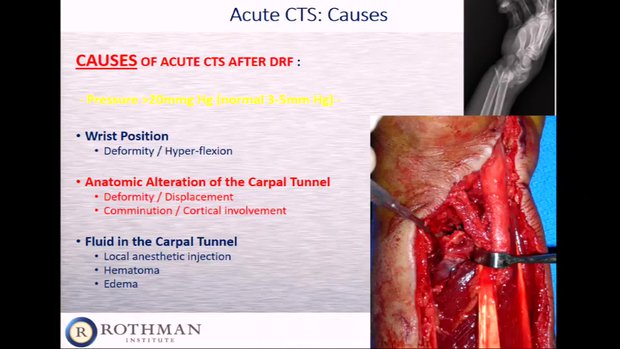

健康・医学 Distal Radius Fractures and Carpal Distal Radius Fractures and Acute Carpal Tunnel Syndromeの詳細情報

Distal Radius Fractures and Acute Carpal Tunnel Syndrome。Complex Regional Pain Syndrome after Distal Radius Fracture。Distal Radius fractures and acute Carpal tunnel syndrome。Acute Carpal Tunnel Syndrome in Pediatric Distal Radius。Distal Radius Fractures and Carpal Instabilities: FESSH IFSSH 2019 Instructional Book (English Edition)新品¥18,560Francisco del Pinal | 2019/6/24